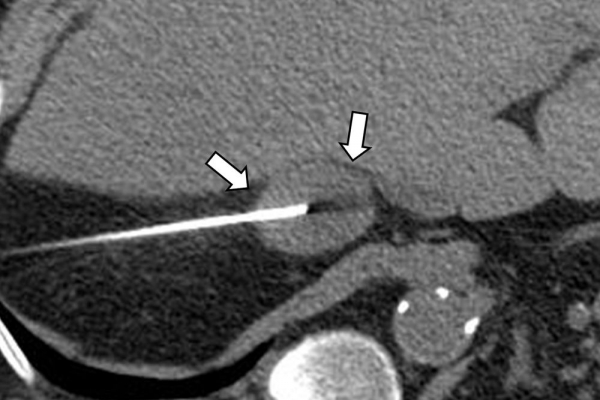

Η διαδερμική βιοψία είναι μία ελάχιστα επεμβατική μέθοδος λήψης υλικού από τον όγκο για κυτταρολογική και ιστολογική εξέταση, από εστιακές αλλοιώσεις του ήπατος, πνεύμονα, νεφρού κλπ. Συστήνεται από τον κλινικό ιατρό ανάλογα με το είδος και το μέγεθος της βλάβης και πραγματοποιείται με ασφάλεια από επεμβατικό ακτινολόγο με την καθοδήγηση αξονικού τομογράφου ή υπερήχων. Στη σύγχρονη ογκολογική θεραπεία όπου γίνεται προσπάθεια καταπολέμησης του καρκίνου σε μοριακό επίπεδο κρίνεται αναγκαία η ακριβής ιστολογική ταυτοποίηση του όγκου ώστε να εφαρμοσθεί εξατομικευμένη θεραπεία για το βέλτιστο αποτέλεσμα. Οι κατευθυνόμενες βιοψίες στοχευουν στο να παρέχουν στον κλινικό ογκολόγο το απαραίτο ιστοπαθολογικό υλικό που θα του επιτρέψει να εφαρμόσει την κατάλληλη θεραπεία για τον ογκολογικό ασθενή.